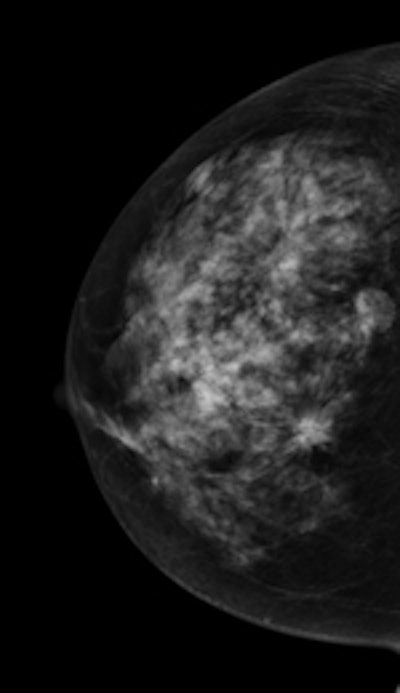

Left: Mediolateral oblique view of a patient with two malignant masses (invasive ductal carcinomas) using mammography. Center: Same patient viewed via craniocaudal mammography. Right: Same patient viewed on DBT. The spicules and tumor structures are better depicted by DBT. Copyright Dr. Gisella Gennaro.

Left: Mediolateral oblique view of a patient with two malignant masses (invasive ductal carcinomas) using mammography. Center: Same patient viewed via craniocaudal mammography. Right: Same patient viewed on DBT. The spicules and tumor structures are better depicted by DBT. Copyright Dr. Gisella Gennaro."Manufacturers are now progressively moving from prototype systems to clinical products, and exposure control is being optimized, allowing the acquisition of a DBT view at the same dose as a single mammography view," the authors noted. "This would permit use of a combined technique, like the one proposed in this work, at the same dose level as the reference standard (two-view digital mammography), with some benefits in terms of clinical performance, or, alternatively, use mediolateral oblique-view DBT alone at comparable performance to that of two-view mammography, but at half the breast dose."